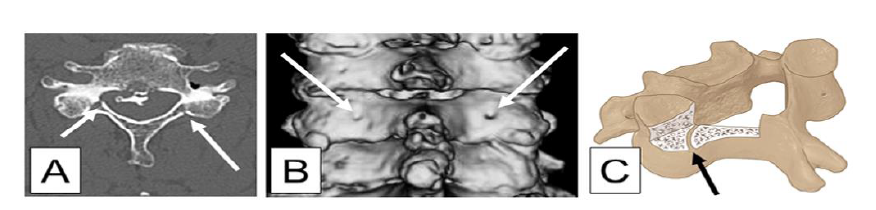

近期有学者发表一项研究[1],探讨颈椎椎板后外侧滋养孔与椎管的关系,以及在脊柱手术中如何利用滋养孔安全有效的进行骨性减压。研究者通过连续观察266例接受颈椎手术治疗的患者,通过三维CT扫描确定了滋养孔与椎管的解剖位置关系。

箭头所示为滋养孔的解剖位置

研究发现约1/3的患者存在颈椎滋养孔。C3-C6滋养孔多位于椎管外侧壁约3mm(平均3.06±1.74mm)的椎板后外侧,未发现位于椎管内侧的营养孔。颈椎节段位置越低,滋养孔离椎管越近。

典型病例:脊髓型颈椎病、后纵韧带骨化症,选择颈椎后路双开门减压术。黑色箭头为滋养孔(被认为硬膜外静脉丛的通道,术中根据情况可能需要使用电凝或骨蜡止血),白色箭头是以滋养孔为地标导航,向内3mm制作的门轴处。

因此认为,可以把颈椎椎板后方的滋养孔作为颈椎椎板减压手术的解剖“地标”,在滋养孔内侧3mm处选择“开门”、制作门轴、椎板切除减压是安全可靠的。同时在颈后路脊柱内镜手术中,滋养孔的出现就像夜空中的北极星一样,也可辅助内镜下的辨识定位,避免镜下迷路。